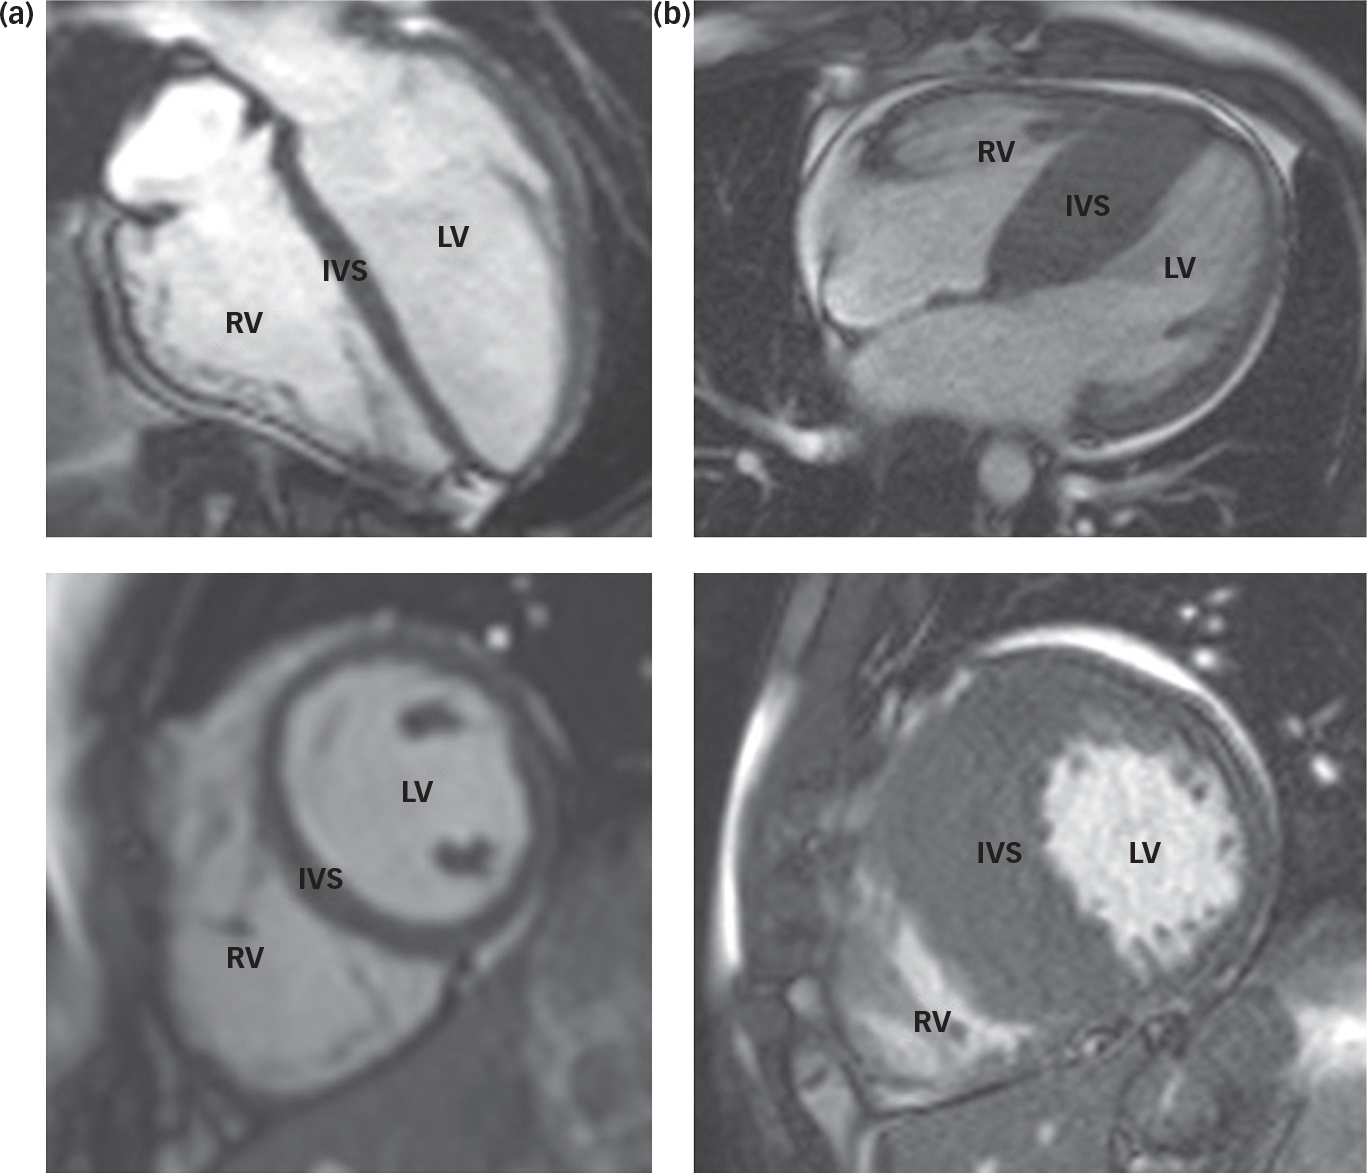

The patient was a 36-year-old British male of Iranian decent with a diagnosis of treatment-resistant schizophrenia. He was single, unemployed and living with his family. He was referred for a trial of clozapine in the context of an established diagnosis of HCM (Fig. 1). At the time of admission, he presented with multimodal hallucinations, thought disorder, delusional beliefs and psychosomatic symptoms; he had no cardiovascular symptoms. On admission, he scored 40 on the Psychotic Symptom Rating Scales (PSYRATS)Reference Haddock, McCarron, Tarrier and Faragher 9 and 80 on the Depression Anxiety Stress Scale (DASS).Reference Lovibond and Lovidbond 10 He had previously trialled a number of antipsychotic agents with limited improvement, including aripiprazole, paliperidone, amisulpride and risperidone. Flupentixol and olanzapine had been moderately successful in treating his positive symptoms, but had to be stopped because of adverse motor effects. At the time of admission, he was on amisulpride 800 mg and sertraline 100 mg for low mood.

Fig. 1 Cardiac magnetic resonance images of a normal heart (a) and a heart demonstrating hypertrophic cardiomyopathy (b). Note the significant increase in muscle mass at the intraventricular septum (IVS) in the abnormal heart (b). LV – left ventricle; RV – right ventricle.

Relevant past medical history includes the diagnosis of HCM, made 3 years prior following the finding of an abnormal ECG. Further diagnostic investigations had included TTE, 24-h Holter monitoring and cardiovascular magnetic resonance imaging (CMR). During the 3-year follow-up period, the patient had been asymptomatic and was not felt to be at significant risk of sudden cardiac death (Table 1). He was taking bisoprolol 7.5 mg daily to treat hypertension – this being the agent of choice in those with HCM to help ameliorate the potential risk of arrhythmic demise and outflow obstruction associated with HCM. Other cardiovascular risk factors include a 17 pack/year smoking history and hypercholesterolaemia controlled with atorvastatin 40 mg daily.